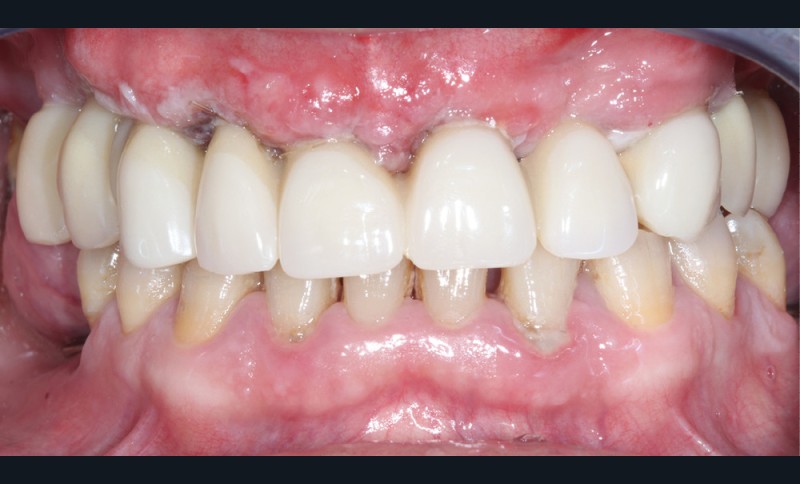

Réévaluation (mars 2022)

Le patient a été satisfait de l’immédiateté et du confort de la restauration provisoire, mais n’a malheureusement pas poursuivi son traitement et n’est venu consulter que quelques années plus tard, avec des répercussions prévisibles et néfastes. L’absence de calage molaire, l’hygiène déficiente (aucun passage de brossette dans les embrasures) et une absence de suivi au cabinet ont entraîné une inflammation très importante des tissus péri-implantaires (fig. 8…